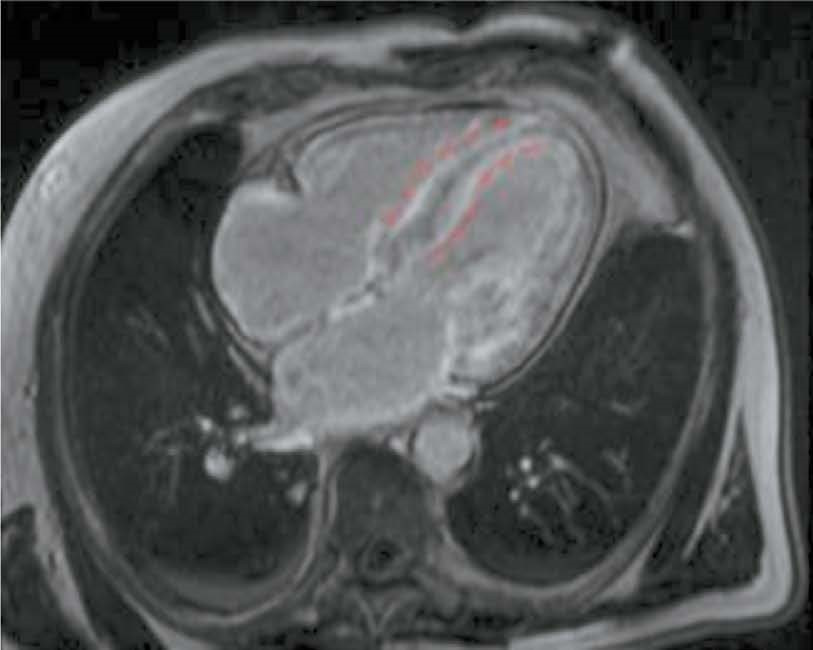

Potential use of cardiac magnetic resonance imaging in differential diagnosis of cardiomyopathies due to light-chain amyloidosis and transthyretin amyloidosis

BACKGROUND: Cardiac amyloidosis is a serious progressive disease with a high mortality rate. The differential diagnosis of cardiomyopathies due to amyloid light-chain (AL) amyloidosis and transthyretin (ATTR) amyloidosis is important for selecting the optimal treatment strategy.

AIM: The aim of this study was to evaluate the capabilities of cardiac magnetic resonance imaging in the differential diagnosis of cardiomyopathies due to AL and ATTR amyloidosis.

MATERIALS AND METHODS: A retrospective analysis of the medical records of 25 patients with a confirmed diagnosis of amyloid cardiomyopathy was performed. Patients were divided into two groups according to the type of amyloidosis, with group 1 including patients with cardiomyopathy due to AL amyloidosis and group 2 including patients with cardiomyopathy due to ATTR amyloidosis. All patients underwent contrast-enhanced cardiac magnetic resonance imaging. Volumetric and linear cardiac parameters, ventricular function, and late gadolinium enhancement patterns were assessed. Standard statistical methods were used, and differences were considered significant at p <0.05.

RESULTS: Group 2 showed a more significant thickening of the myocardial walls compared to group 1 (interventricular septum: 18 [17; 18] vs. 14.5 mm [12.8; 16.0], p <0.01, posterior wall of the left ventricle: 14 [13; 17] vs. 10.5 mm [10; 12.3], p <0.01). The indexed mass of the left ventricle myocardium was 110 [92; 125] in group 2 and 85 mm [69.3; 91.8] in group 1 (p <0.01). In group 2, late gadolinium enhancement with a transmural left ventricle pattern was more frequently observed in the basal and mid-lower-lateral segments, whereas in group 1, a subendocardial pattern of late gadolinium enhancement was more frequent in the mid-anterior and lower-lateral segments (p <0.05). In addition, frequency of simultaneous contrast enhancement in the subendocardial layers of the interventricular septum on the left ventricle and right ventricle sides was higher in group 2 (100% of cases vs. 50%, p <0.01). Late gadolinium enhancement of the right ventricle was also more common in group 2 (100 vs. 58%, p <0.05), especially in the interventricular septum and inferior wall area (p <0.05). Semi-quantitative assessment of LGE using the Query Amyloid Late Enhancement (QALE) showed greater contrast enhancement in group 2: 13 [12; 14] vs. 10.5 [1.75; 12], p <0.01), and a score greater than 13 differentiated between cardiomyopathy due to AL amyloidosis and ATTR amyloidosis with a sensitivity of 69% and a specificity of 83%.

CONCLUSIONS: Cardiac MRI identifies typical features of cardiomyopathies due to AL amyloidosis and ATTR amyloidosis for their differential diagnosis. Further research is needed to confirm diagnostic accuracy of the patterns identified.